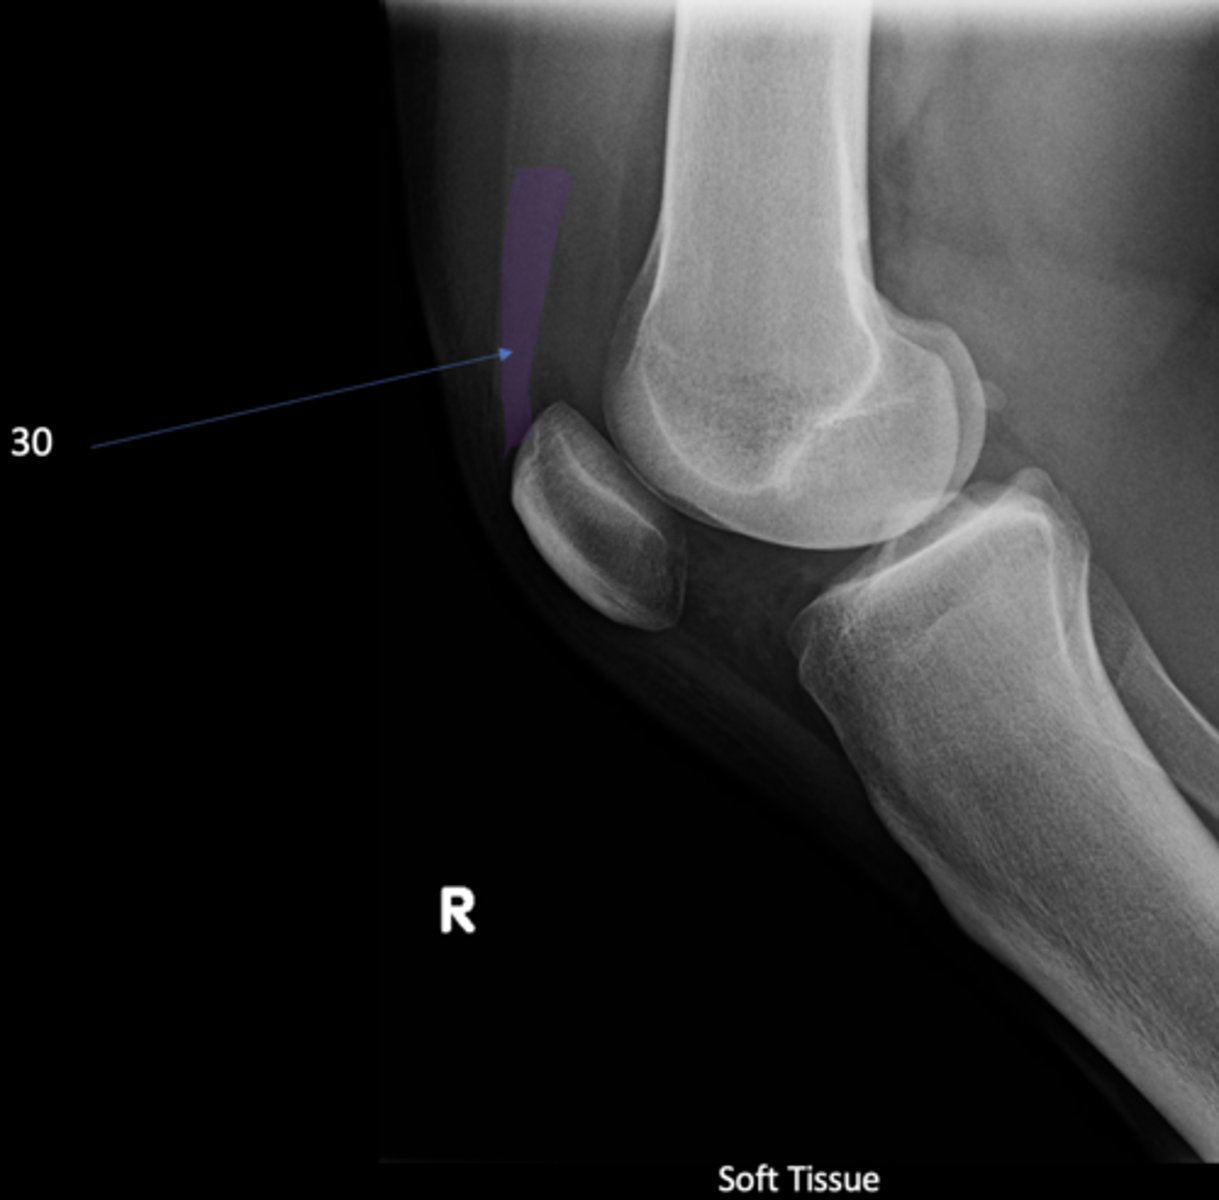

- AP knee

- Lateral knee

- Tunnel (intercondylar) knee

State the standard knee projections

Lateral knee

ID standard knee projection

<p>ID standard knee projection</p>

Flexion

Lateral knee projections are generally taken with _____

<p>Lateral knee projections are generally taken with _____</p>

Infrapatellar pouch

ID 29

92

New cards

Hoffa's fat pad

Another term for infrapatellar pouch

<p>Another term for infrapatellar pouch</p>

Quadriceps tendon

ID 30

<p>ID 30</p>

Prefemoral fat pad

ID 31

<p>ID 31</p>

Suprapatellar pouch

ID 32

<p>ID 32</p>

Ludloff's patch/spot

- Not a true anatomical structure

- Appears due to less bone being traversed anteriorly than posteriorly